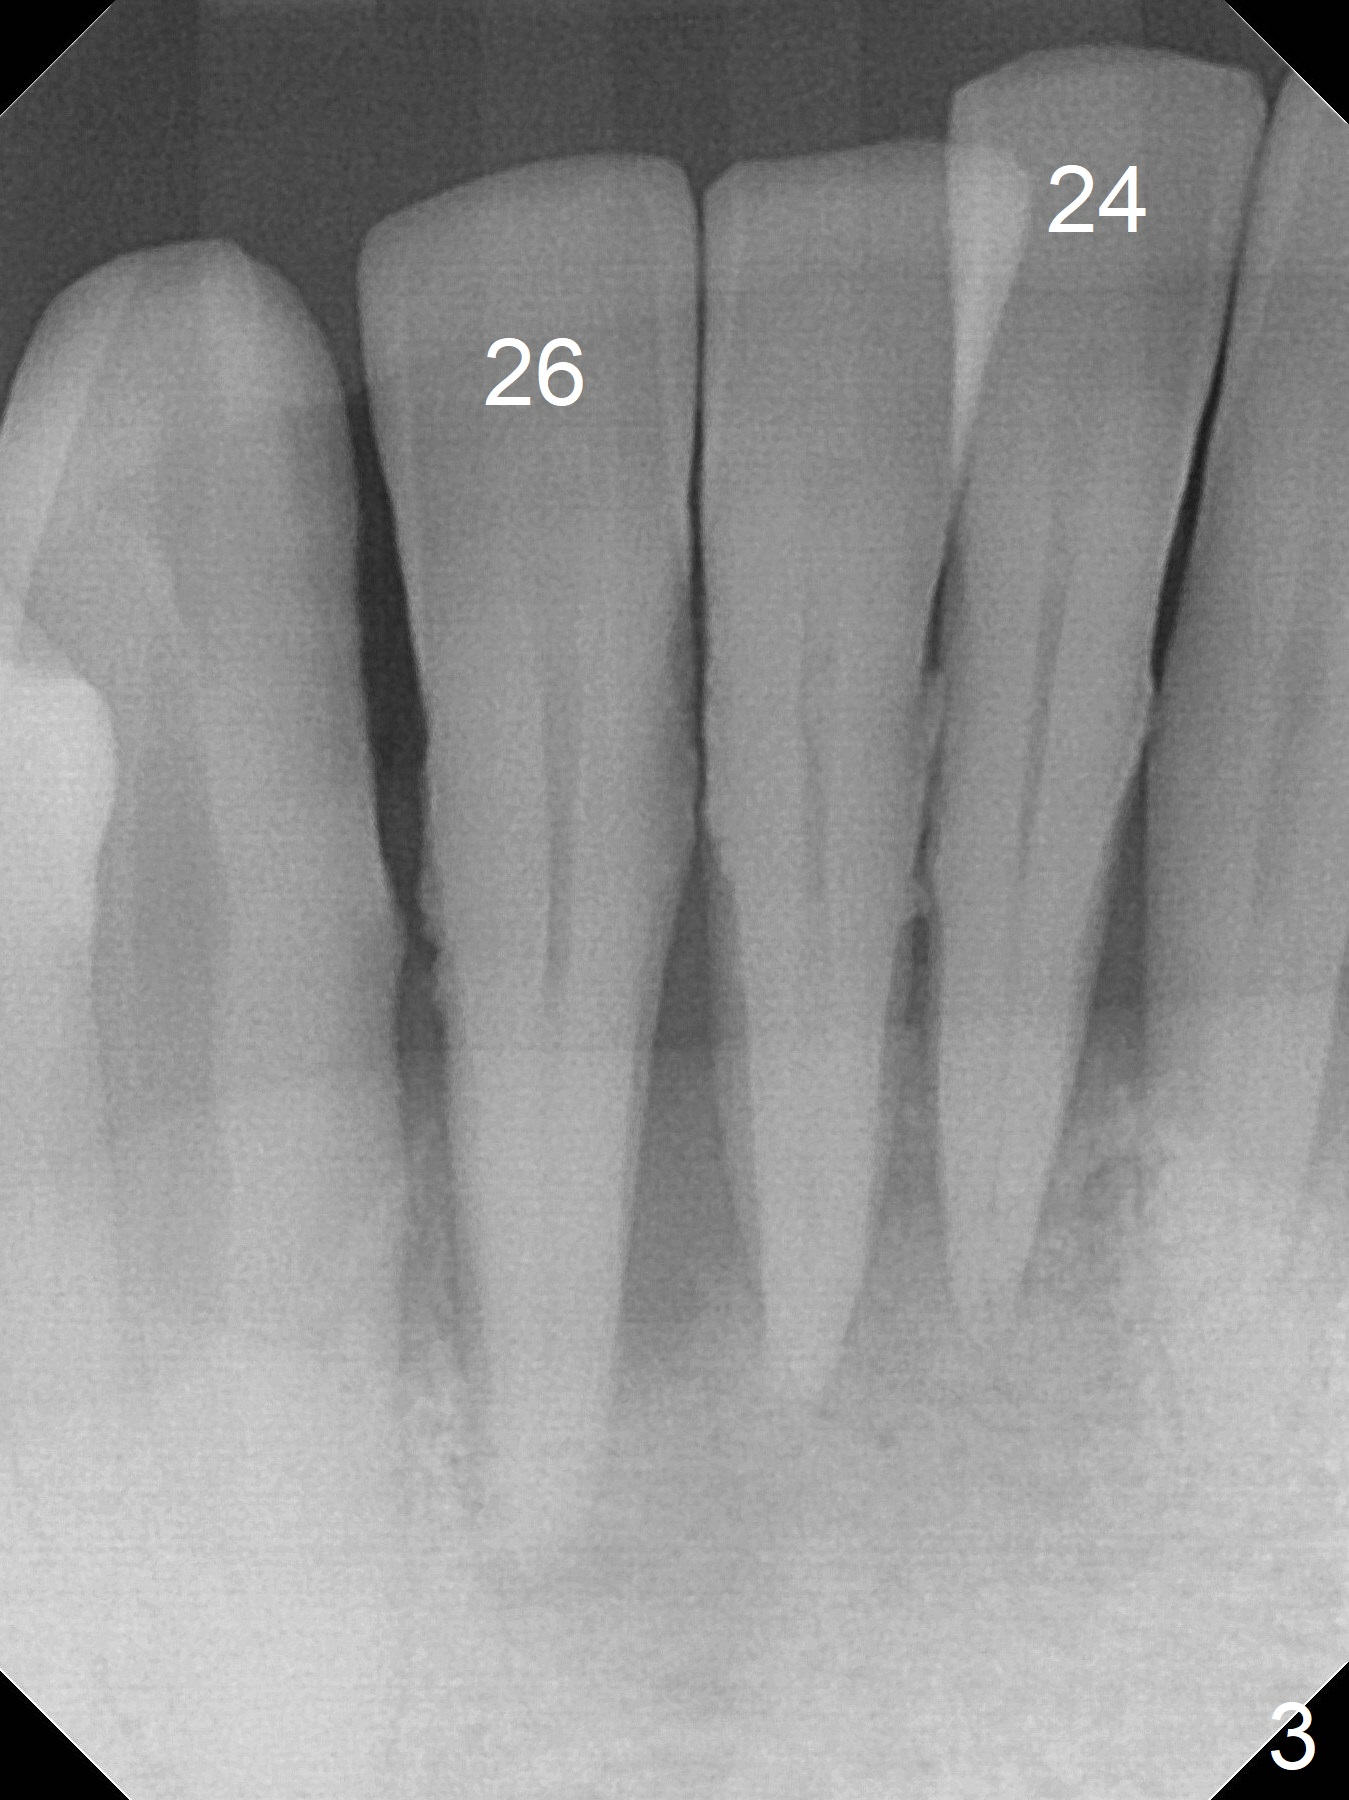

A 45-year-old man requests implant replacement for #5, 9 and 24-26 (Fig.1) after extraction of the tooth #9 (Fig.2). The teeth #24-26 have severe bone loss with mobility III (Fig.3). Since their roots are close to each other (Fig.4 (after extraction)), osteotomy will be initiated at #24 and 26 (Fig.5).